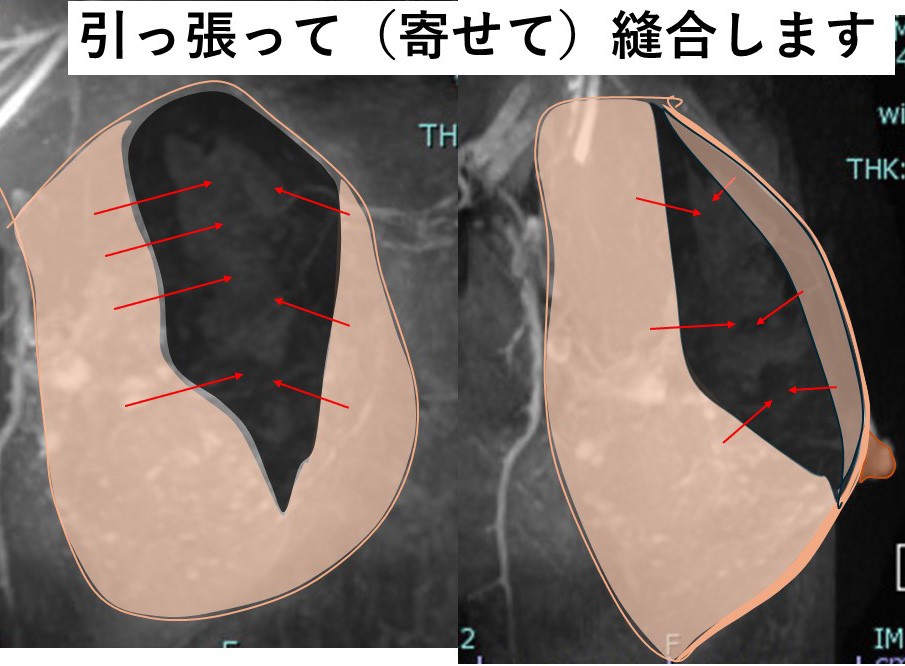

6. 乳腺の(欠損部の)縫合

乳腺の端と端を縫合します。

結構大きい欠損なのに、乳腺がそんなに(縫合できるほど)伸びるのか??

8. それには訳があります。

乳腺は「厚み」があるので、それを「薄く引き伸ばす」イメージです。